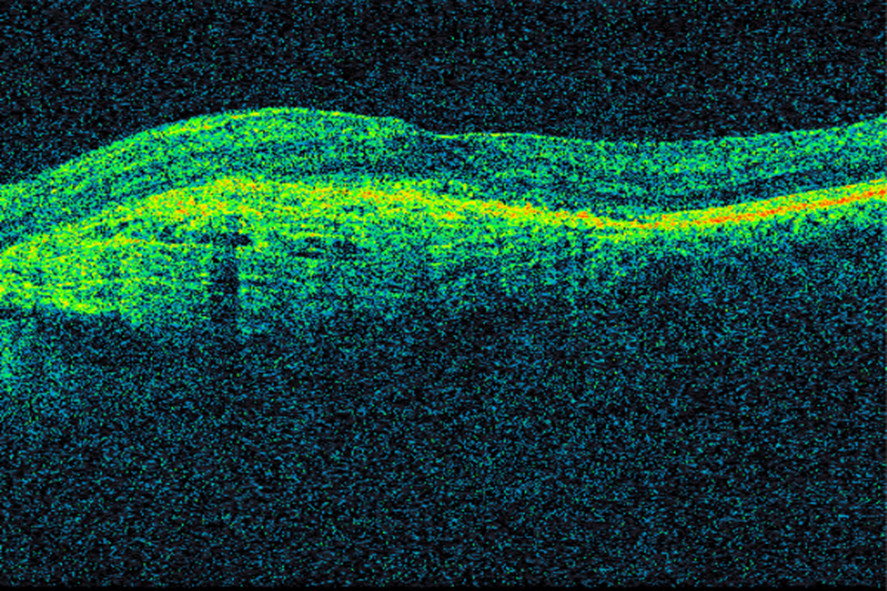

Samtidig som bevacizumab ble tatt i bruk på kreftpasienter, ble VEGF-hemmeren pegaptanib (Macugen) godkjent i USA for behandling av våt aldersrelatert makuladegenerasjon (3). Pegaptanib nøytraliserer VEGF165, som er en av de fire isoformene av vaskulær endotelial vekstfaktor. Pegaptanib fikk raskt konkurranse. Kort tid etter at bevacizumab ble godkjent for kolorektal kreft, ble det gitt til pasienter med våt makuladegenerasjon. En liten studie viste klar bedring av visus, redusert netthinnetykkelse og mindre lekkasje fra neovaskulære forandringer etter bevacizumab gitt intravenøst (13). Amerikanske øyeleger begynte deretter å injisere medikamentet intravitrealt (direkte i øyets glasslegeme) (14). Norske øyeavdelinger var tidlig ute med å tilby denne behandlingen. Intravitreale injeksjoner med VEGF-hemmere er meget effektivt i behandlingen av våt aldersrelatert makuladegenerasjon og andre øyesykdommer, og innebærer lav risiko for komplikasjoner og bivirkninger (15, 16). I denne sammenhengen må det nevnes at utviklingen av optisk koherens-tomografi (optical coherence tomography, OCT) i øyefaget har hatt stor klinisk, vitenskapelig og økonomisk betydning. Optisk koherens-tomografi er en hurtig og ikke-invasiv undersøkelsesmetode som ved hjelp av lysbølger avbilder øyets anatomiske strukturer med mikrometer-oppløsning (17) (figur 1). Teknologien anvendes i dag innen de fleste av øyefagets underspesialiteter, men især ved diagnostisering og oppfølging av øyesykdommer som rammer netthinnen og den utenforliggende årehinnen. Figur 2 og 3 viser OCT-bilder av makula med våt aldersrelatert makuladegenerasjon i samme pasient før og etter oppstart med anti-VEGF-behandling.

Figur 1 Optisk koherens-tomografi (OCT) som viser normal makula. I midten ses fovea centralis, hvor tettheten av…

Figur 1 Optisk koherens-tomografi (OCT) som viser normal makula. I midten ses fovea centralis, hvor tettheten av fotoreseptorer er høyest. Tverrsnittsbilder av netthinnen muliggjør blant annet vurdering av morfologien og måling av netthinnens tykkelse.